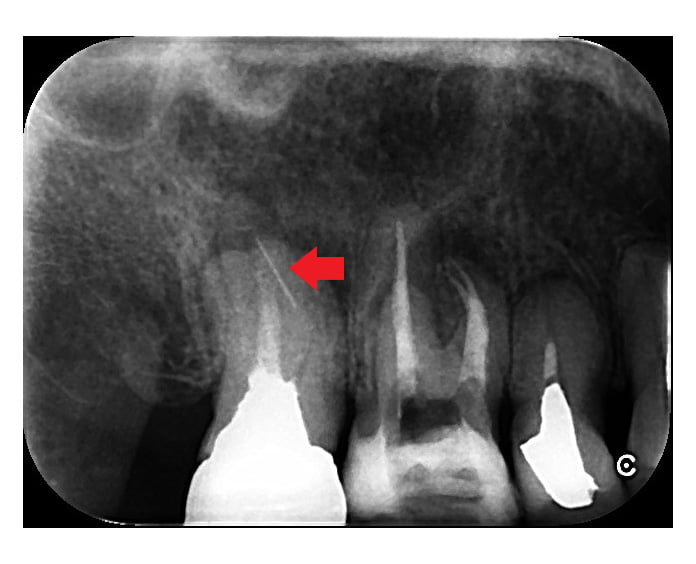

下の画像は、破折ファイルが根管を塞ぎ膿の治療を阻んでいるケースです。CT画像で歯根の先に膿の影がみられますが、破折ファイルが根管を塞いでいるため、このままでは再根管治療によって根管に残る細菌感染を除去し膿を改善することができません。根管治療によって歯を残すために、まさに破折ファイル除去が必要なケースです。(但し、根の周りに膿などの病変がなく根管内に細菌感染が無いことが考えられる場合は、破折ファイルは除去しなくても良いことがあります)